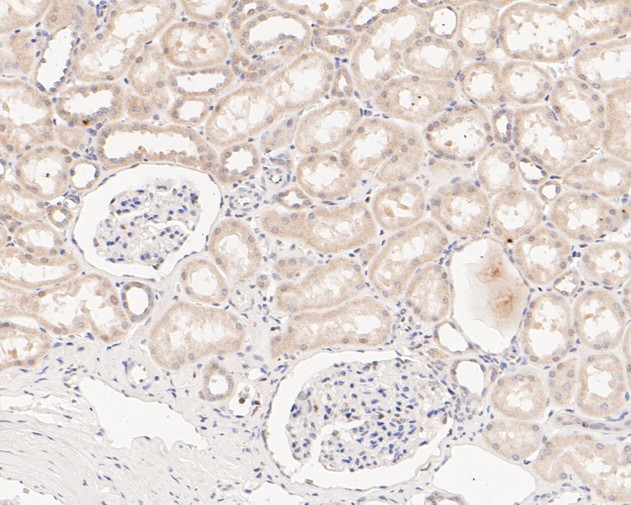

|   | Fig4: Immunohistochemical analysis of paraffin-embedded human kidney tissue using anti-SENP2 antibody. The section was pre-treated using heat mediated antigen retrieval with sodium citrate buffer (pH 6.0) for 20 minutes. The tissues were blocked in 5% BSA for 30 minutes at room temperature, washed with ddH2O and PBS, and then probed with the primary antibody (ET7110-33, 1/50) for 30 minutes at room temperature. The detection was performed using an HRP conjugated compact polymer system. DAB was used as the chromogen. Tissues were counterstained with hematoxylin and mounted with DPX. |